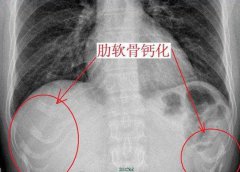

用于隆鼻的硅胶钙化是什么意思?假体需要切除吗?

导读:不管做隆鼻还是隆胸,对于假体的选择都需要较为慎重,那么硅胶隆鼻20年后假体会钙化吗?如果出现了钙化对身体有什么影响呢? 我想做一个硅胶假体用于隆鼻,但是我对硅胶假